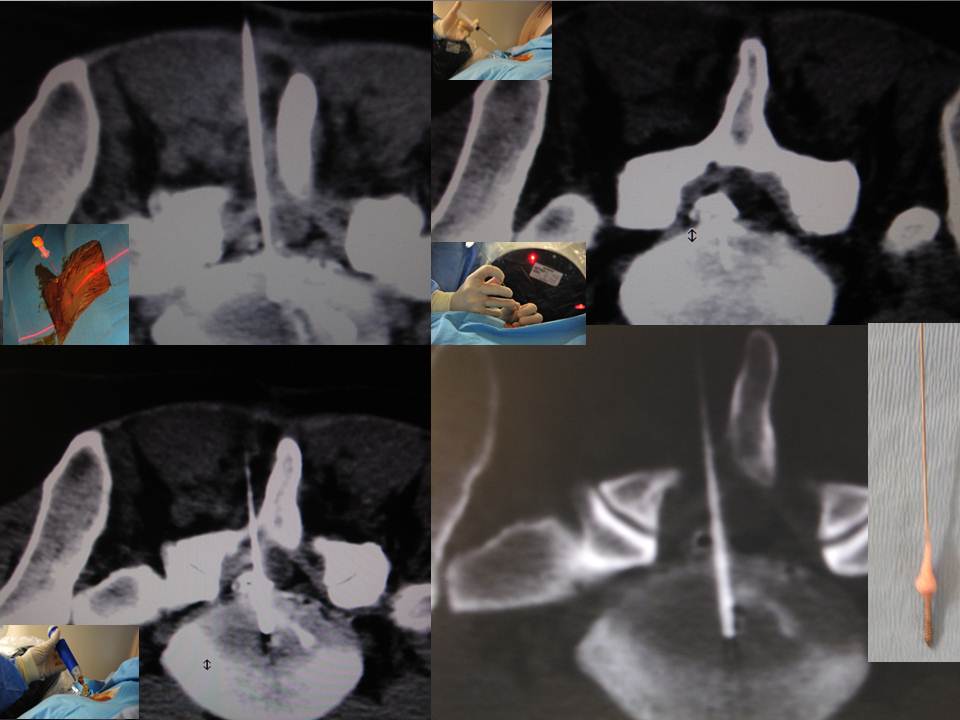

Herniectomies